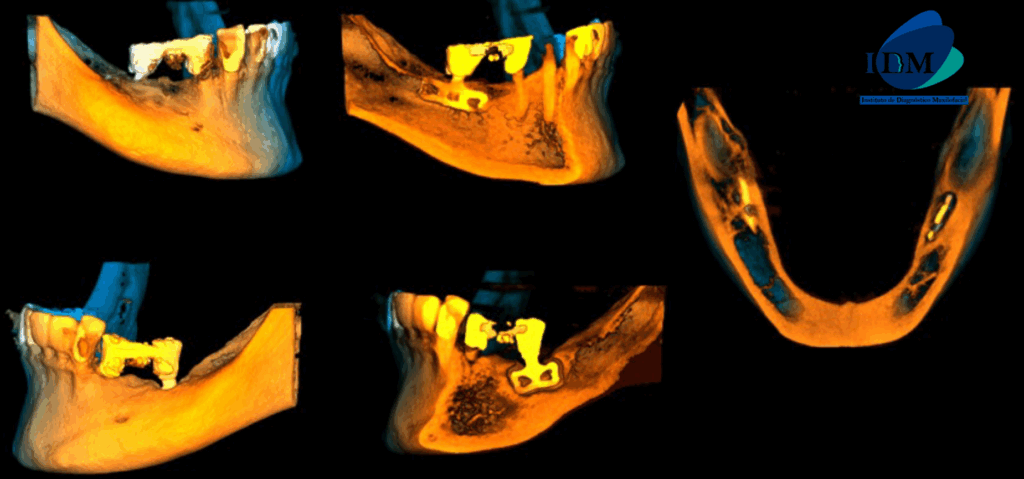

Al observar la tomografía computarizada de campo mediano se puede observar que los implantes en el maxilar inferior son efectivamente de tipo laminares o de lámina perforada, además se puede observar en vistas axiales la presencia de una imagen hipodensa circundante al implante de zona de pieza 36 (flecha azul), en vistas transaxiales y tangenciales se evidencian pérdida de continuidad de tejido óseo en tercio cervical; características que no presenta el implante en zona de pieza 46 (flecha amarilla- vista axial). Signos imagenológicos compatible con perimplantitis.

RECONSTRUCCIÓN 3D